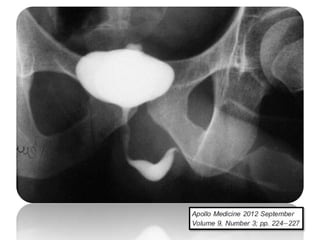

PRESENTACIÓN CLÍNICA

Las pacientes pueden manifestar dolor crónico,

infertilidad o sangrado vaginal.

En algunos casos pueden presentar síntomas agudos

similares a la enfermedad inflamatoria pélvica por

otras causas.

Cuando se sospeche la enfermedad, la

histerosalpingografía se indica. Prácticamente todos las

pacientes tendrán hallazgos anormales.

Varios criterios diagnósticos se han descrito: los ganglios

linfáticos calcificados o calcificaciones pequeñas en las

regiones anexiales, obstrucción del tubo entre el istmo

y la ampolla, adherencias endometriales y en las

trompas sin antecedentes de legrado o aborto.